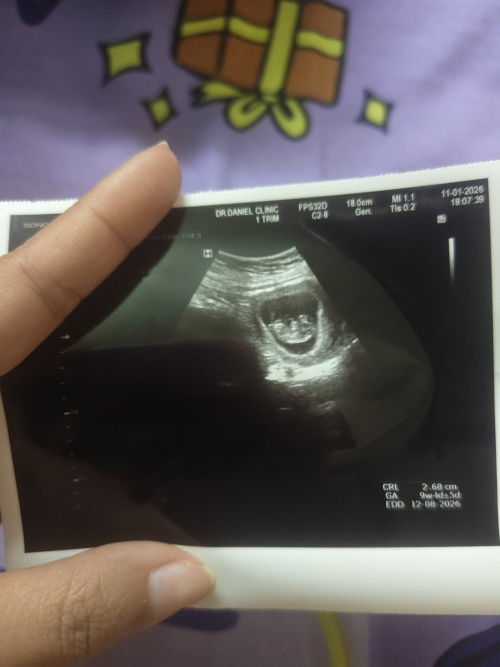

จากเมื่อวานที่ได้หาหมอ เพราะอาการเลือดออกที่ช่องคลอดเป็นสีน้ำตาลไม่เยอะมากมีอาการปวดท้องน้อยร่วมด้วยเหมือนมีอะไรแทงที่มดลุก หมออัลต้าซาวบอกว่าถุงตั้งครรภ์ยังอยุ่ดีที่มีเลือดออกเพราะมดลุกขยาย วันนี้ที่ 16 ได้มาโรงบาลอีกรอบเพราะอาการเดิมแต่ปวดมากกว่าเดิมและมีเลือดสีสดออกมากกว่าเดิมออกเหมือนประจำเดือนมา หมออัลต้าซาวให้และตรวจภายในผลสรุปคือแท้ง หมอเวรวันนี้เลยถามหาหมอที่เข้าเวรตรวจเมื่อวานว่าทำไมถึงไม่ให้แอดมิดตั้งแต่เมื่อวานขี้เกียจหรืออะไรกันตั้งครรภ์อายุครรภ์แค่7สัปดาห์มันเสี่ยงมาก เราเลยอยากบอกแม่ๆทุกท่านเพื่อเป็นอุทาหร หมอไม่ได้ห่วงคนไข้ทุกคนเสมอไป เราเสียใจมากที่เลือกโรงบาลผิดตั้งใจมากกลับลุกคนนี้เพราะมีลุกยากอายุ 41 โอกาสมีก็น้อย#ขอบคุณสำหรับคอมเม้นล่วงหน้าค่ะ